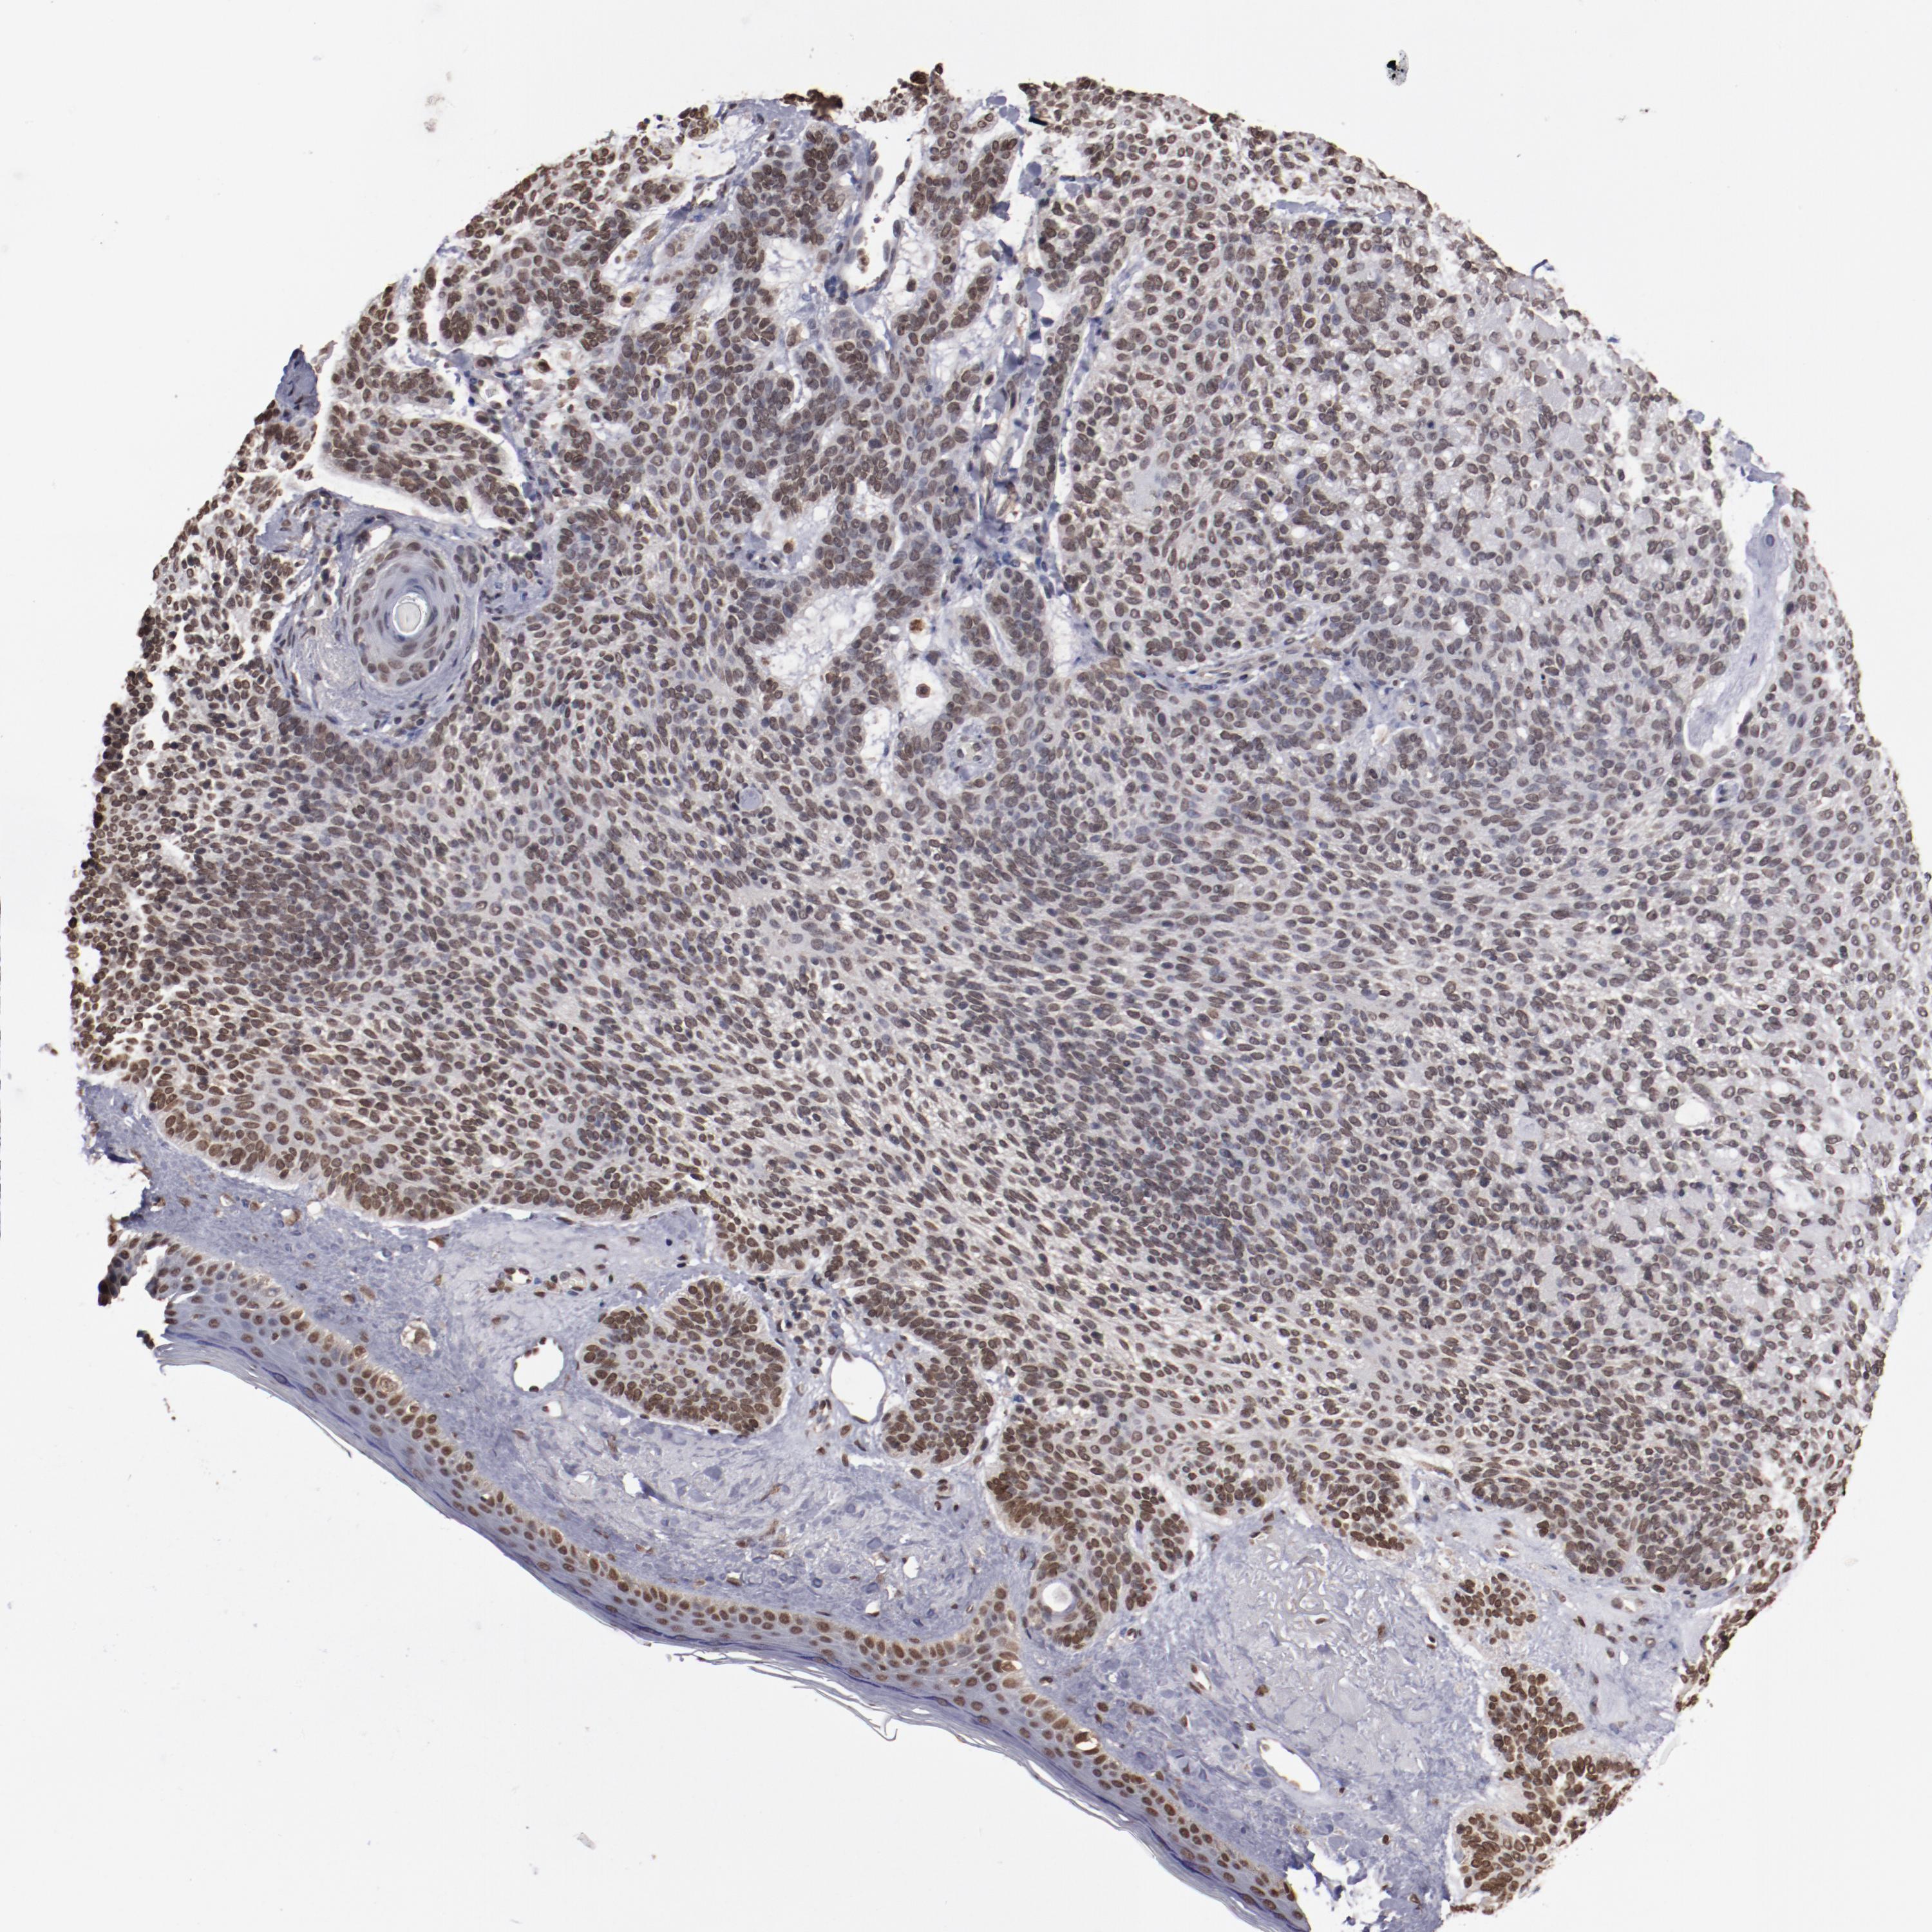

CANCER SKIN CANCER Show tissue menu

Basal cell and squamous cell cancer

SKIN CANCER - Protein expressioni

A mouse-over function shows sample information and annotation data. Click on an image to view it in a full screen mode. Samples can be filtered based on level of antibody staining by selecting one or several of the following categories: high, medium, low and not detected. The assay and annotation is described here.

Each image is clickable and will lead to virtual microscopy that enables deeper exploration of all samples and also displays staining intensity scores, fraction scores and subcellular localization as well as patient and tissue information for each sample.

Antibody CAB003765

Squamous cell carcinoma, NOS

Basal cell carcinoma